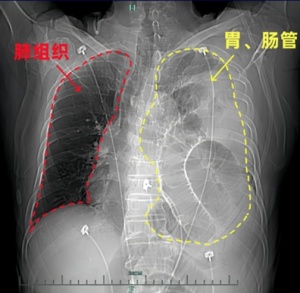

烧伤的程度是80%”